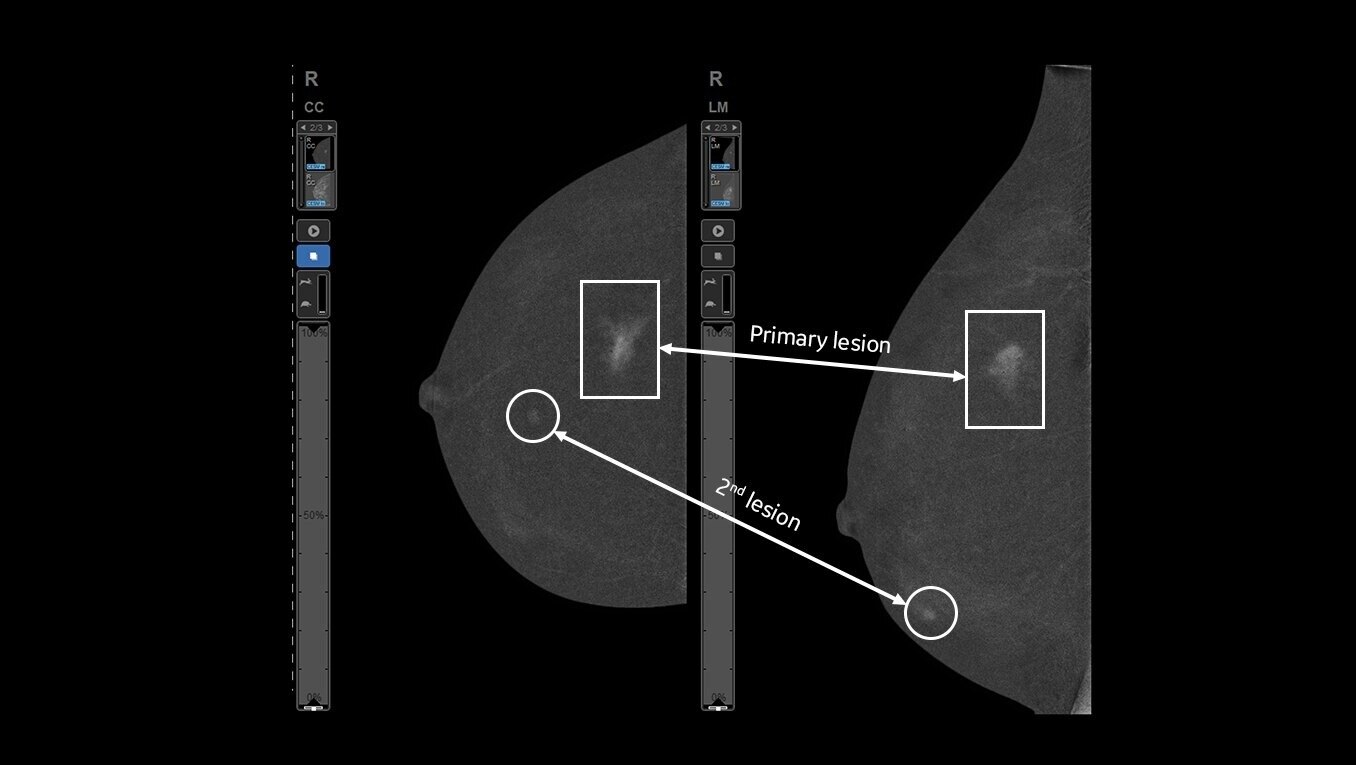

Avoid the challenges of seeking correlating lesions in MRI. CEM allows you to see lesions clearly and sample with certainty with the same image guidance.

With high sensitivity and specificity, CEM helps drive accuracy in biopsy. It allows you to clearly target suspicious areas by correlating lesion locations already identified in your patient’s diagnostic enhanced mammogram.